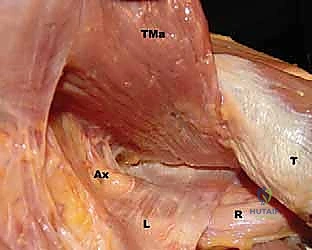

FIG 1 • A. Cadaveric dissection showing the interval between the teres major (TMa) and latissimus dorsi (L) tendons, with the radial nerve (R) deep to the latissimus and the axillary nerve (Ax) superior.

- Axillary Nerve: The axillary nerve runs superior to the latissimus dorsi tendon before exiting the quadrangular space. In neural rotation and adduction, the average distance between the nerve and the superior border of the tendon is 1.9 cm. Like the radial nerve, this distance increases with external rotation and abduction and decreases with internal rotation.

FIG 1 • C. Cadaveric dissection of the superficial muscular anatomy of the posterior shoulder, showing the axillary nerve (Ax) exiting the quadrilateral space.